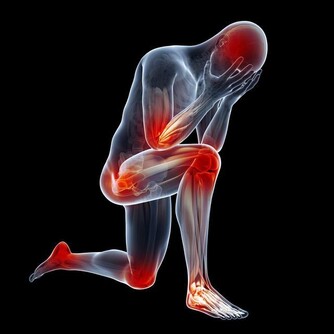

老年人由於身體各方面機能下降,運動要以自身能接受為宜,可適當進行快走等運動方式,避免長時間爬樓、爬山等,以免損傷膝關節。